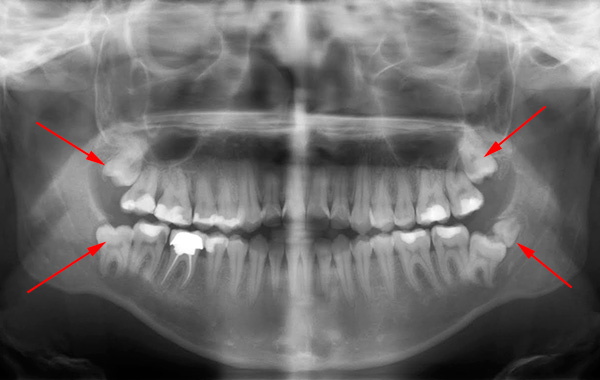

Il seguente è un esempio di un dente del giudizio orizzontale nella mascella: